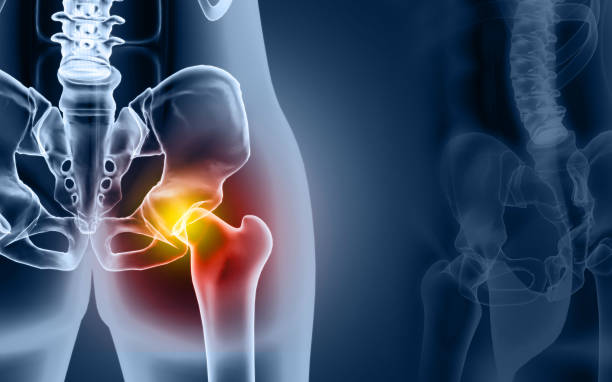

✅고관절 통증 증상 허리디스크? 복합?

이게 고관절이 아프면 단순 통증이라 생각을 하십니다.

단순히 해당 부위에 염증 때문에 발생하는 통증일수도 있습니다.

혹은 허리디스크 때문에 그럴 수도 있습니다. 다양한 복합적인 요인이 있는데요.

고관절 통증의 일반적인 원인 중 하나는 허리디스크입니다. 허리디스크는 허리 부위의 디스크에 문제가 생겨 발생하며, 이로 인해 통증을 겪게 됩니다. 하지만 모든 고관절 통증이 허리디스크로 연결되지는 않습니다. 고관절 주변에도 다양한 원인이 숨어 있을 수 있습니다.

고관절 통증은 종종 단일 원인뿐만 아니라 복합적인 문제에서 비롯됩니다. 이것이 진단과 치료를 어렵게 만들 수 있습니다. 예를 들어, 허리디스크와 함께 관절 주위의 염증, 근육 문제, 혹은 다른 구조적 문제가 동시에 발생할 수 있습니다.